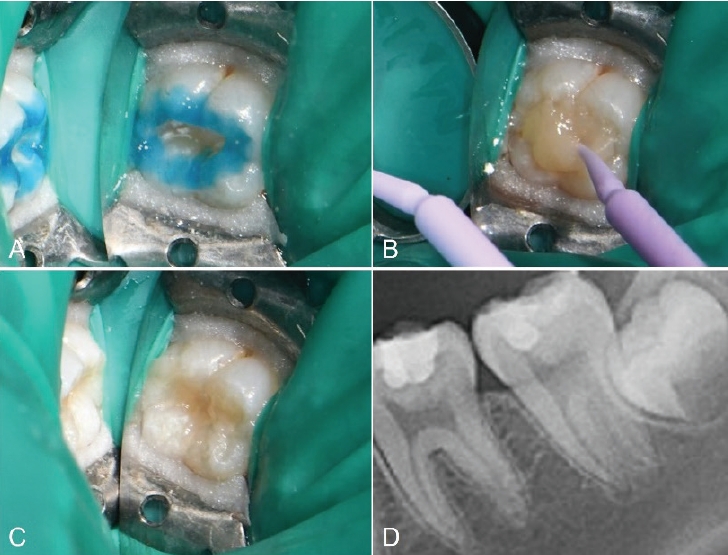

치료 전 1:100000 epinephrine을 포함하는 2% Lidocaine(Yuhan Corp, Seoul, Korea)으로 우측 하악 구치부 전달마취를 시행하였다. 러버댐을 이용하여 격리를 시행하고 주수 하에 Prophy brush를 사용해 교합면을 세정하였다. 이후 유동형 복합레진(Tetric N-Flow, Ivoclar Vivadent, Schaan, Liechtenstein) 을 교합면에 적용하고 마이크로브러시의 팁을 손잡이로 사용하기 위해 복합레진에 위치시킨 뒤 광중합하여 스탬프를 형성하였다. 그 후, 일반적인 와동 형성 프로토콜에 따라 우식 제거를 시행하였다. round diamond bur를 이용하여 고속 핸드피스로 주수 하에 우식을 제거하였다. 법랑질 먼저 10초간 35% phosphoric acid로 산부식한 뒤 상아질에 10초간 추가로 산부식하고 수세하였다(Fig. 4A). 약하게 공기를 분사하여 수분을 제거한 뒤 3-step etch-and-rinse system인 Adper Scotchbond Multi-Purpose Bond의 primer를 microbrush로 5초간 도포하고, 공기 분사 후 adhesive를 microbrush로 5초간 도포하고 공기 분사한 뒤 LED 광중합기로 10초간 광중합하였다. 이후 Microhybrid계 복합레진인 Filtek Z250를 이용해 교합면에서 2mm 아래까지 수복하고 20초간 광중합하였다. 최종 복합레진 적층 전 테플론 테이프를 교합면에 덮고 제작한 스탬프를 정밀하게 위치시켜 가볍게 압력을 주었다(Fig. 4B). 스탬프 및 테플론 테이프를 조심스럽게 제거한 뒤 과잉 재료를 레진 기구로 정리하고 광중합하였다(Fig. 4C). 교합지와 심스탁을 이용한 교합 검사 후 교합 조정을 시행하였다. Sof-lex spiral로 수복물 연마를 시행하였다.